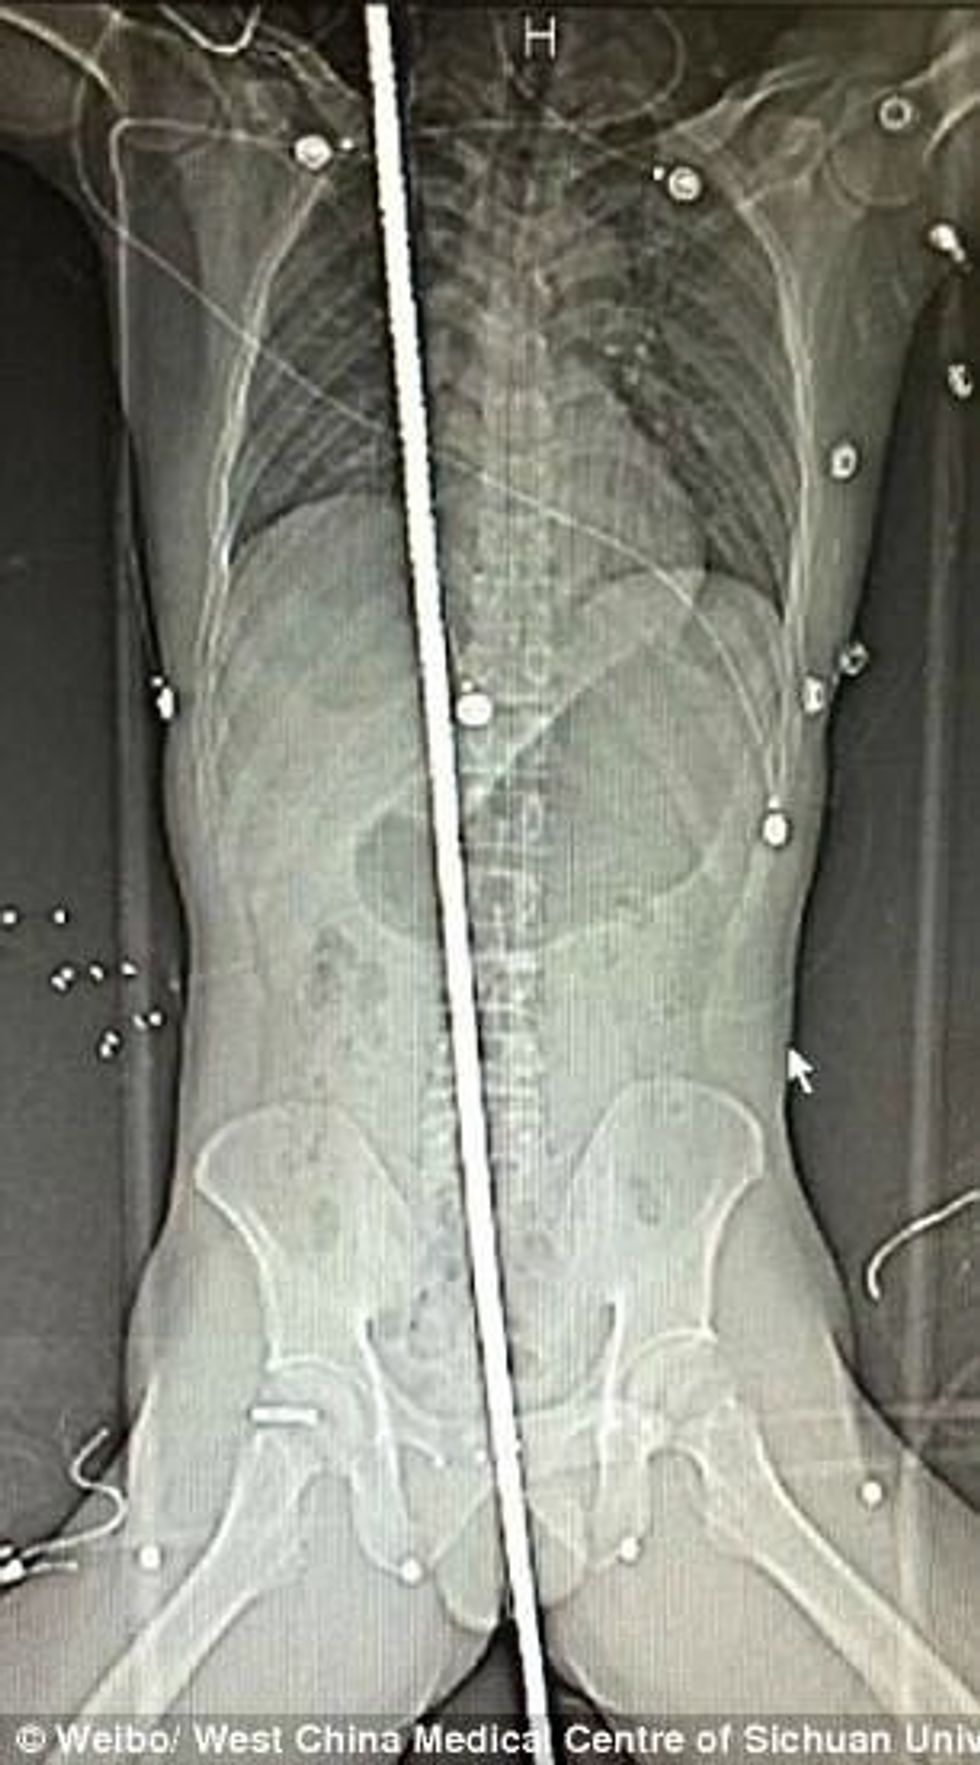

Punonjësi i paemëruar që ndodhej në një punishte në Kinë, ka rënë në armaturën e gjatë dy metra, pasi ka humbur kontrollin kur është goditur nga vetëtima.

Shufra metalike që i hyri 37-vjeçarit përmes zonës intime, i kaloi nëpër tërë trupin për t’i dalë te qafa, transmeton Telegrafi.

Për fat të mirë, atij nuk i është dëmtuar asnjë organ vital, duke shpëtuar pa dëme serioze.

Mjekët që ia larguan nga trupi, kanë kërkuar për ndonjë infektim që ka mundur të pësonte, por fatmirësisht ai ka gjendje shumë të mirë shëndetësore. /Telegrafi/